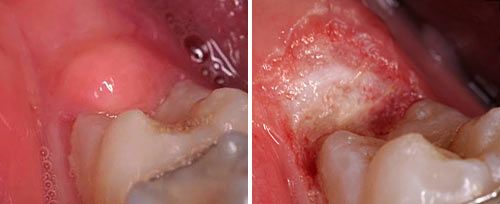

Oral Surgery

Clinical Results